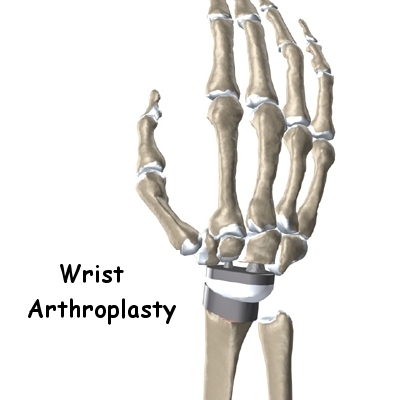

The wrist joint is replaced with an artificial joint (also called a prosthesis) much less often than other joints in the body, such as the knee or the hip. Still, when necessary, this operation can effectively relieve the pain caused by wrist arthritis. When severe arthritis has destroyed the wrist joint, artificial wrist replacement surgery (also called wrist arthroplasty) can help restore wrist strength and motion for many patients.

The part that replaces the small wrist bones is called the distal component. This piece is made completely of metal. It is globe shaped to fit into the plastic socket on the end of the radius. The metal distal component is attached by two metal stems that fit into the hollow bone marrow cavities of the carpal and metacarpal bones of the hand.

The plastic used in artificial joints is tough and slick. It allows the two pieces of the new joint to glide easily against each other as you move your wrist. The ball and socket allow movement of the wrist in all directions.